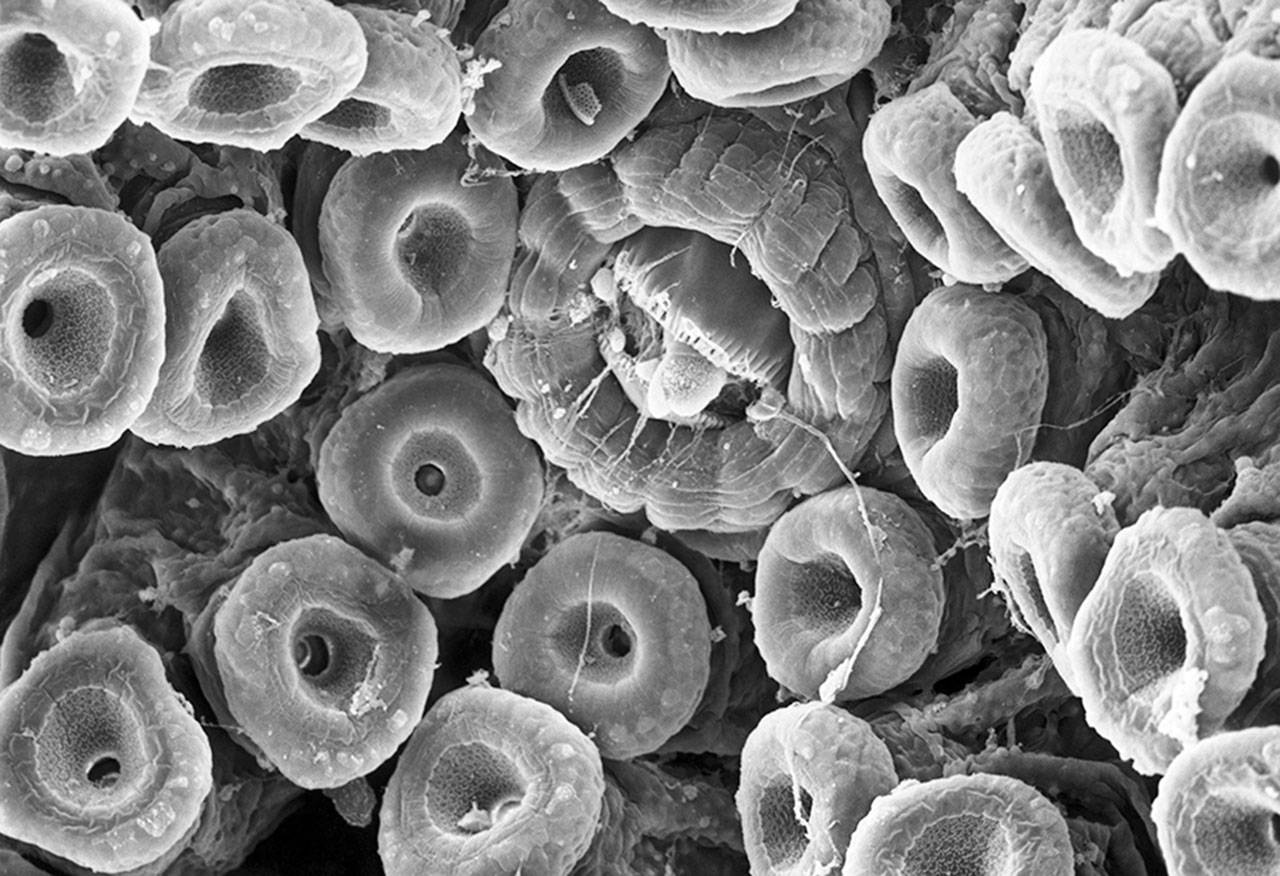

Фотографии биологических объектов: микроскопические снимки